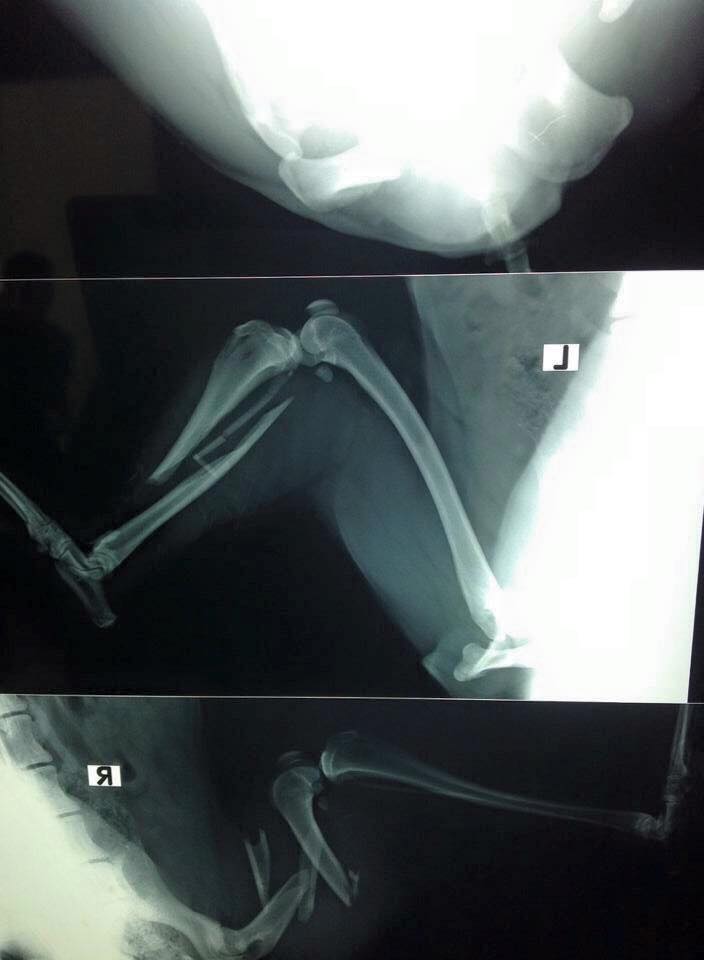

This little puppy was hit by a vehicle as well. His both hind limbs and pelvis has terrible fractured. Kept him for two days under care and couldn’t find any solution, hence had to euthanise him.

Rest in peace little pup. You had to leave this cruel world with No name. Hope you will find a good name there in heaven.